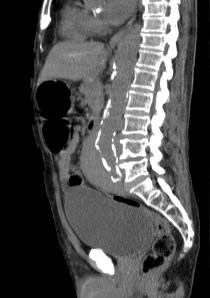

SIGNO DE LA AORTA FLOTANTE (Floating aorta sign):

Representa el crecimiento y coalescencia de conglomerados adenopáticos que desplazan la aorta lumbar hacia adelante, despegándola de la columna. Este signo lo producen algunos tumores, en especial el Linfoma. Así, da la impresión de que la aorta está «flotando» inmersa en una masa de partes blandas retroperitoneal que se ha formado por el crecimiento de las adenopatías de las cadenas periaórticas, pericavas e interaortocavas, las cuales finalmente se han unido. Otro signo muy útil es el signo del Sandwich, donde se observa, en un TC con contraste, como la masa envuelve los vasos y la grasa del mesenterio.